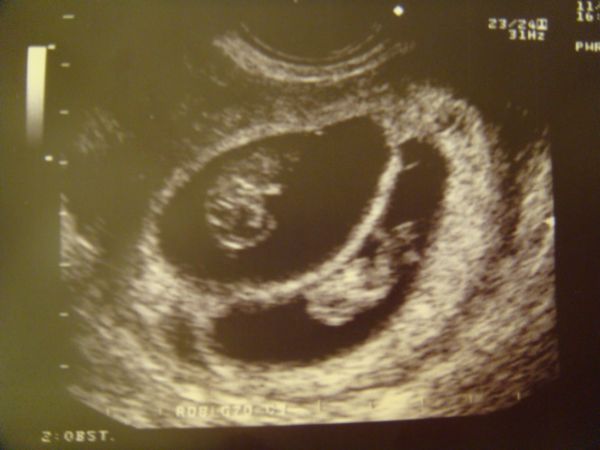

Két babó

Kép

1 babó

Sajnos egyszerre nem férnek rá. :lol: